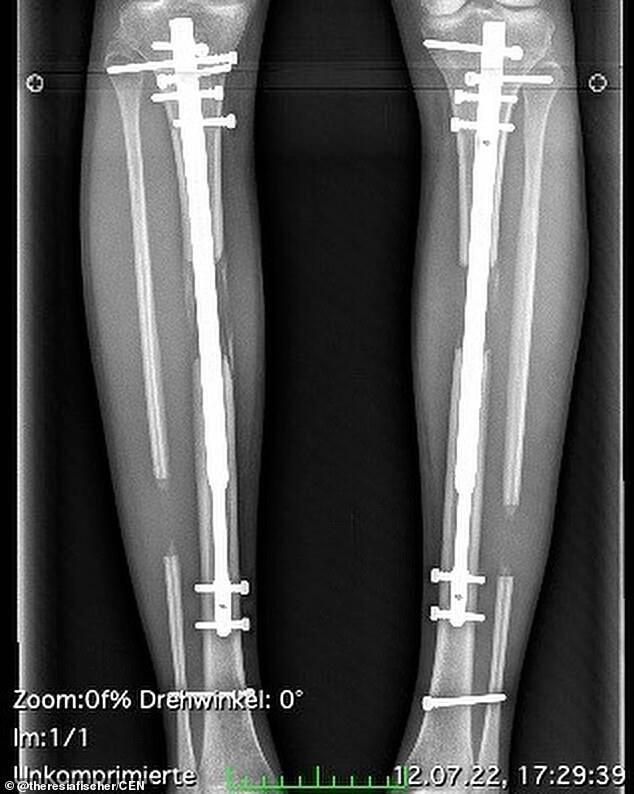

“在手术过程中6英尺1英寸是多少厘米,胫骨被干净地折断,小腿肌肉被分开,并且每次都使用伸缩杆,”特雷西亚在接受采访时这样解释了手术的过程。“你可以用一只手握住膝盖,用另一只手向内拧动脚,直到听到咔哒声,从而独立地伸展小腿。每天每侧点击十次,就会增加0.5毫米。”

特雷西亚在24岁时接受了第一次手术,双腿变长了约8.3厘米。去年3月她又进行了第二次手术,这一次延长了5.3厘米。两次加起来共13.6厘米(约14厘米),也让她一跃成为了拥有超过1米8身高的女士,再加上“恨天高”的高度,妥妥是身高2米的“大女人”了。